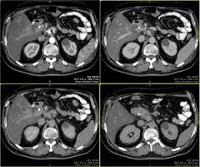

Компьютерная томография брюшной полости и забрюшинного пространства. Высокоскоростное рентгеновское сканирование, позволяющее получать срезы внутренних органов с минимальной толщиной и их трехмерные изображения. Компьютерная томография брюшной полости включает исследование поджелудочной железы, печени и желчного пузыря, селезенки, кишечника; Компьютерная томография забрюшинного пространства - почки, мочевыводящие пути, надпочечники, лимфатические узлы. Исследование этой анатомической области является информативным для выявления воспалительных и опухолевых процессов, поражения органов, мочекаменной болезни, причин механической желтухи, гепатомегалии и спленомегалии и других патологий. Компьютерная томография брюшного и забрюшинного пространства часто выполняется с контрастным усилением (внутривенно, орально или клизма).

Сканирование органов брюшной полости. Современный метод лучевой диагностики с использованием компьютерных программ для обработки данных. Позволяет получить трехмерное изображение печени, кишечника, желчных протоков, брюшных ганглиев, кровеносных сосудов, а также почек, надпочечников, забрюшинных лимфатических узлов и других анатомических структур брюшной полости и забрюшинное пространство. Высокая скорость сканирования, способность распознавать даже небольшие изменения и небольшие патологические очаги, низкая радиационная нагрузка и приемлемая цена для сканера брюшной полости в Москве делают эту методику одним из основных методов диагностики. ряда патологических состояний.